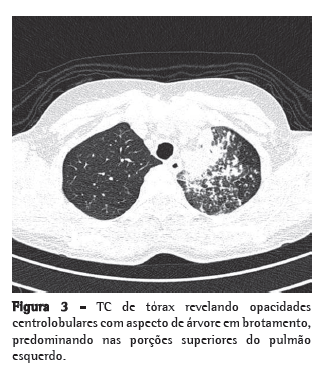

Negava tabagismo e etilismo. A paciente informou ter realizado prova tuberculínica (PT), cujo resultado foi não reator, antes do início do uso de adalimumabe, e que a radiografia de tórax naquela ocasião era normal segundo o médico reumatologista que a acompanhava. Após o uso de azitromicina (há três meses e meio) ainda recebeu mais uma infusão de adalimumabe. Ao exame físico, apresentava-se discretamente hipocorada, sem adenomegalias palpáveis. Presença de estertores finos em terço superior de hemitórax esquerdo e estertores grossos em terço médio de hemitórax direito, além de roncos esparsos. Deformidades articulares em mãos e pés. A radiografia de tórax demonstrava opacidades alveolares no lobo superior esquerdo, lobo inferior esquerdo e lobo médio, além de imagens sugestivas de disseminação broncogênica (Figura 2). A TC de tórax demonstrava opacidades centrolobulares com aspecto de árvore em brotamento (Figura 3).